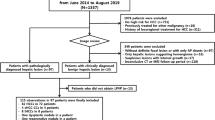

This prospective single-center study was approved by our Institutional Review Board. Signed informed consent was obtained from all patients. Inclusion criteria for our study were as follows: adult patients with liver disease and suspected PH, scheduled for a clinically indicated HVPG measurement within 3 months of MRI (either in combination with a transjugular biopsy or as part of a transjugular intrahepatic portosystemic shunt (TIPS) placement). Exclusion criteria were as follows: history of liver transplant, ongoing beta-blocker treatment, or portal vein occlusion. A total of 36 patients who matched the eligibility criteria were enrolled in our study between March 2018 and January 2020. One patient was excluded because the time between MRI and HVPG measurement exceeded 3 months. Of the final 35 included patients, 22 were male and average age was 55 years (range 22–79 years). Thirty-three patients underwent HVPG measurements, which were indicated due to suspicion of PH. The remaining 2 patients underwent TIPS placement due to refractory ascites. The etiologies of liver disease were as follows: non-alcoholic fatty liver disease/steatohepatitis (NAFLD/NASH), n = 11; autoimmune hepatitis, n = 5; chronic hepatitis infection C, n = 4; primary sclerosing cholangitis, n = 4; cryptogenic cirrhosis, n = 3; non-cirrhotic portal hypertension, n = 3; alcohol- or drug-induced liver disease, n = 2; non-specific reactive hepatitis, n = 2; hemochromatosis, n = 1. The MRI was performed either before or after HVPG measurement. In patients scheduled for TIPS placement, MRI was always performed before the procedure. The average absolute delay between HVPG measurement and MRI was 22 ± 19 days (range 0–78 days).